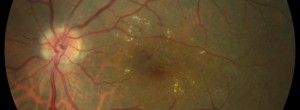

Reappraisal of geographic atrophy patterns seen on fundus autofluorescence using a latent class analysis approach.